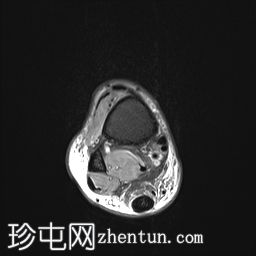

轴位

PD

可见前距腓韧带部分撕裂。

可见后距腓韧带和跟腓韧带轻度扭伤。

骨间韧带未见异常。

三角韧带复合体未见异常。